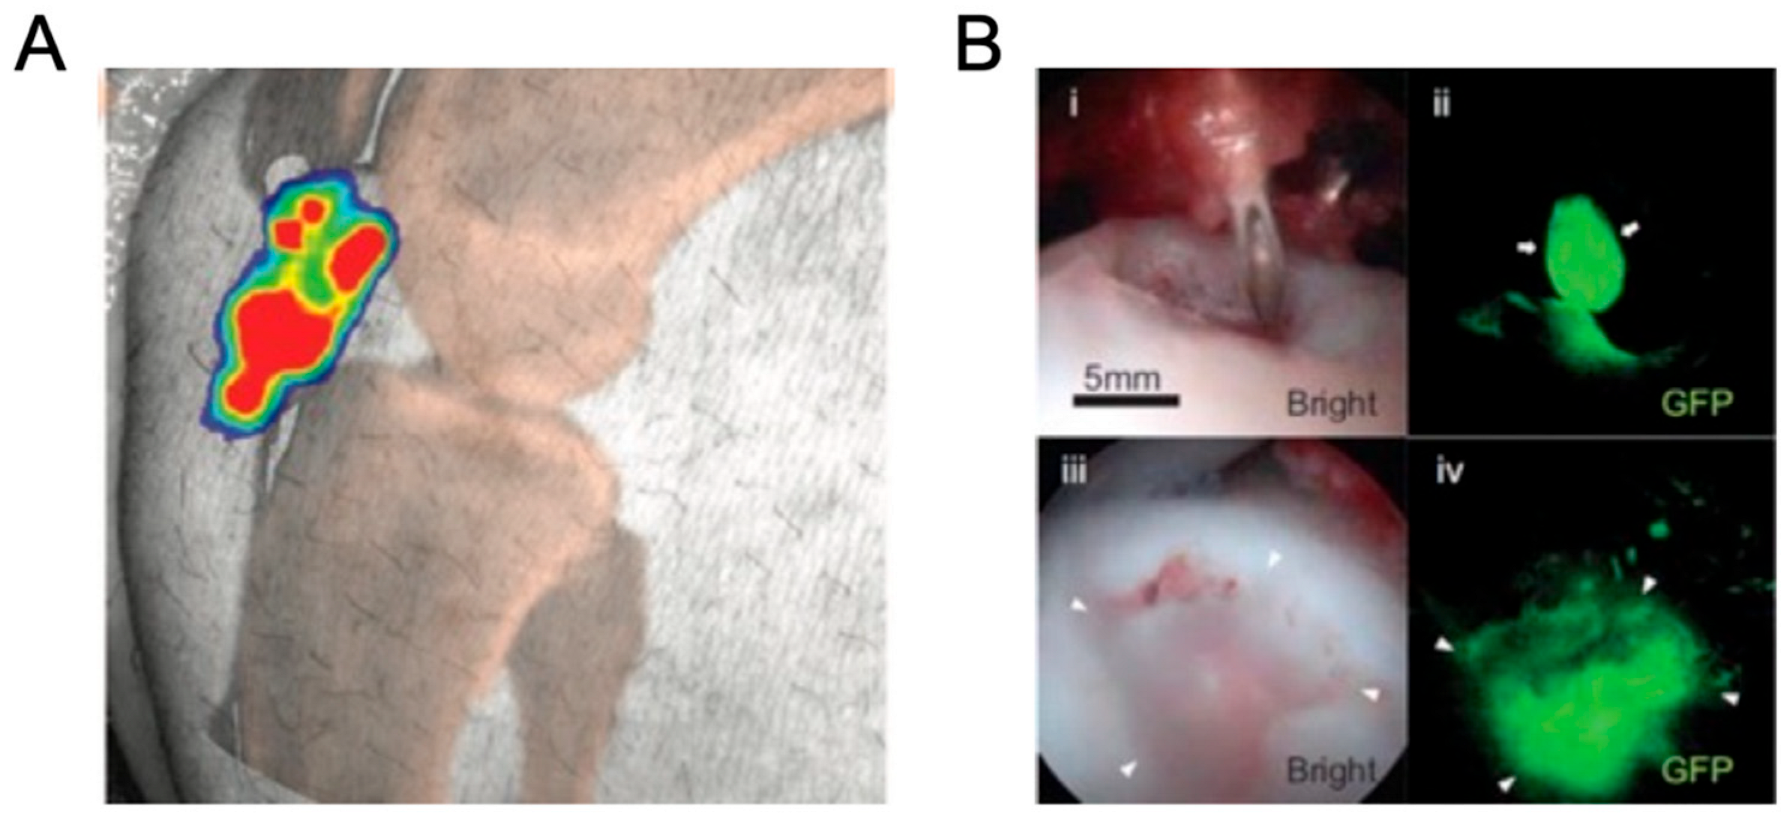

- Pilz, J.; Gloddek, N.; Lindheimer, F.; Lindner, M.J.; Puhr-Westerheide, D.; Ümütlü, M.; Cyran, C.; Seidensticker, M.; Lindner, R.; Kraetzl, M.; et al. Functional maturation and longitudinal imaging of intraportal neonatal porcine islet grafts in genetically diabetic pigs. Am. J. Transplant. 2024, 24, 1395–1405. [Google Scholar] [CrossRef] [PubMed]

- Abe, T.; Endo, K.; Hanazono, Y.; Kobayashi, E. In vivo luciferin–luciferase reaction in pigs using xenogeneic rat bone marrow transplantation: A case report and consideration of recent advance. Int. J. Mol. Sci. 2024, 25, 8609. [Google Scholar] [CrossRef] [PubMed]